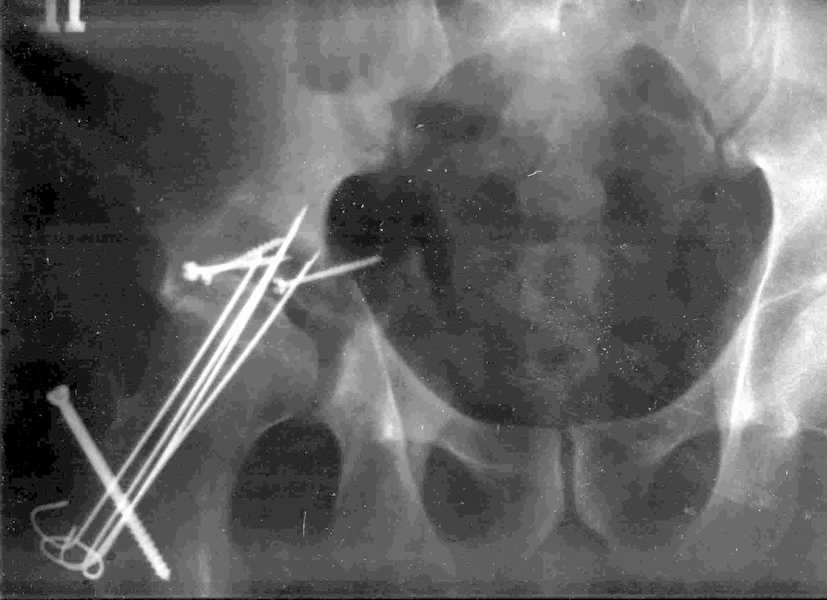

Xray2

Высылаю прямой обзорный и косой подвзошный снимки, косой запирательный неудовлетворительного качества.